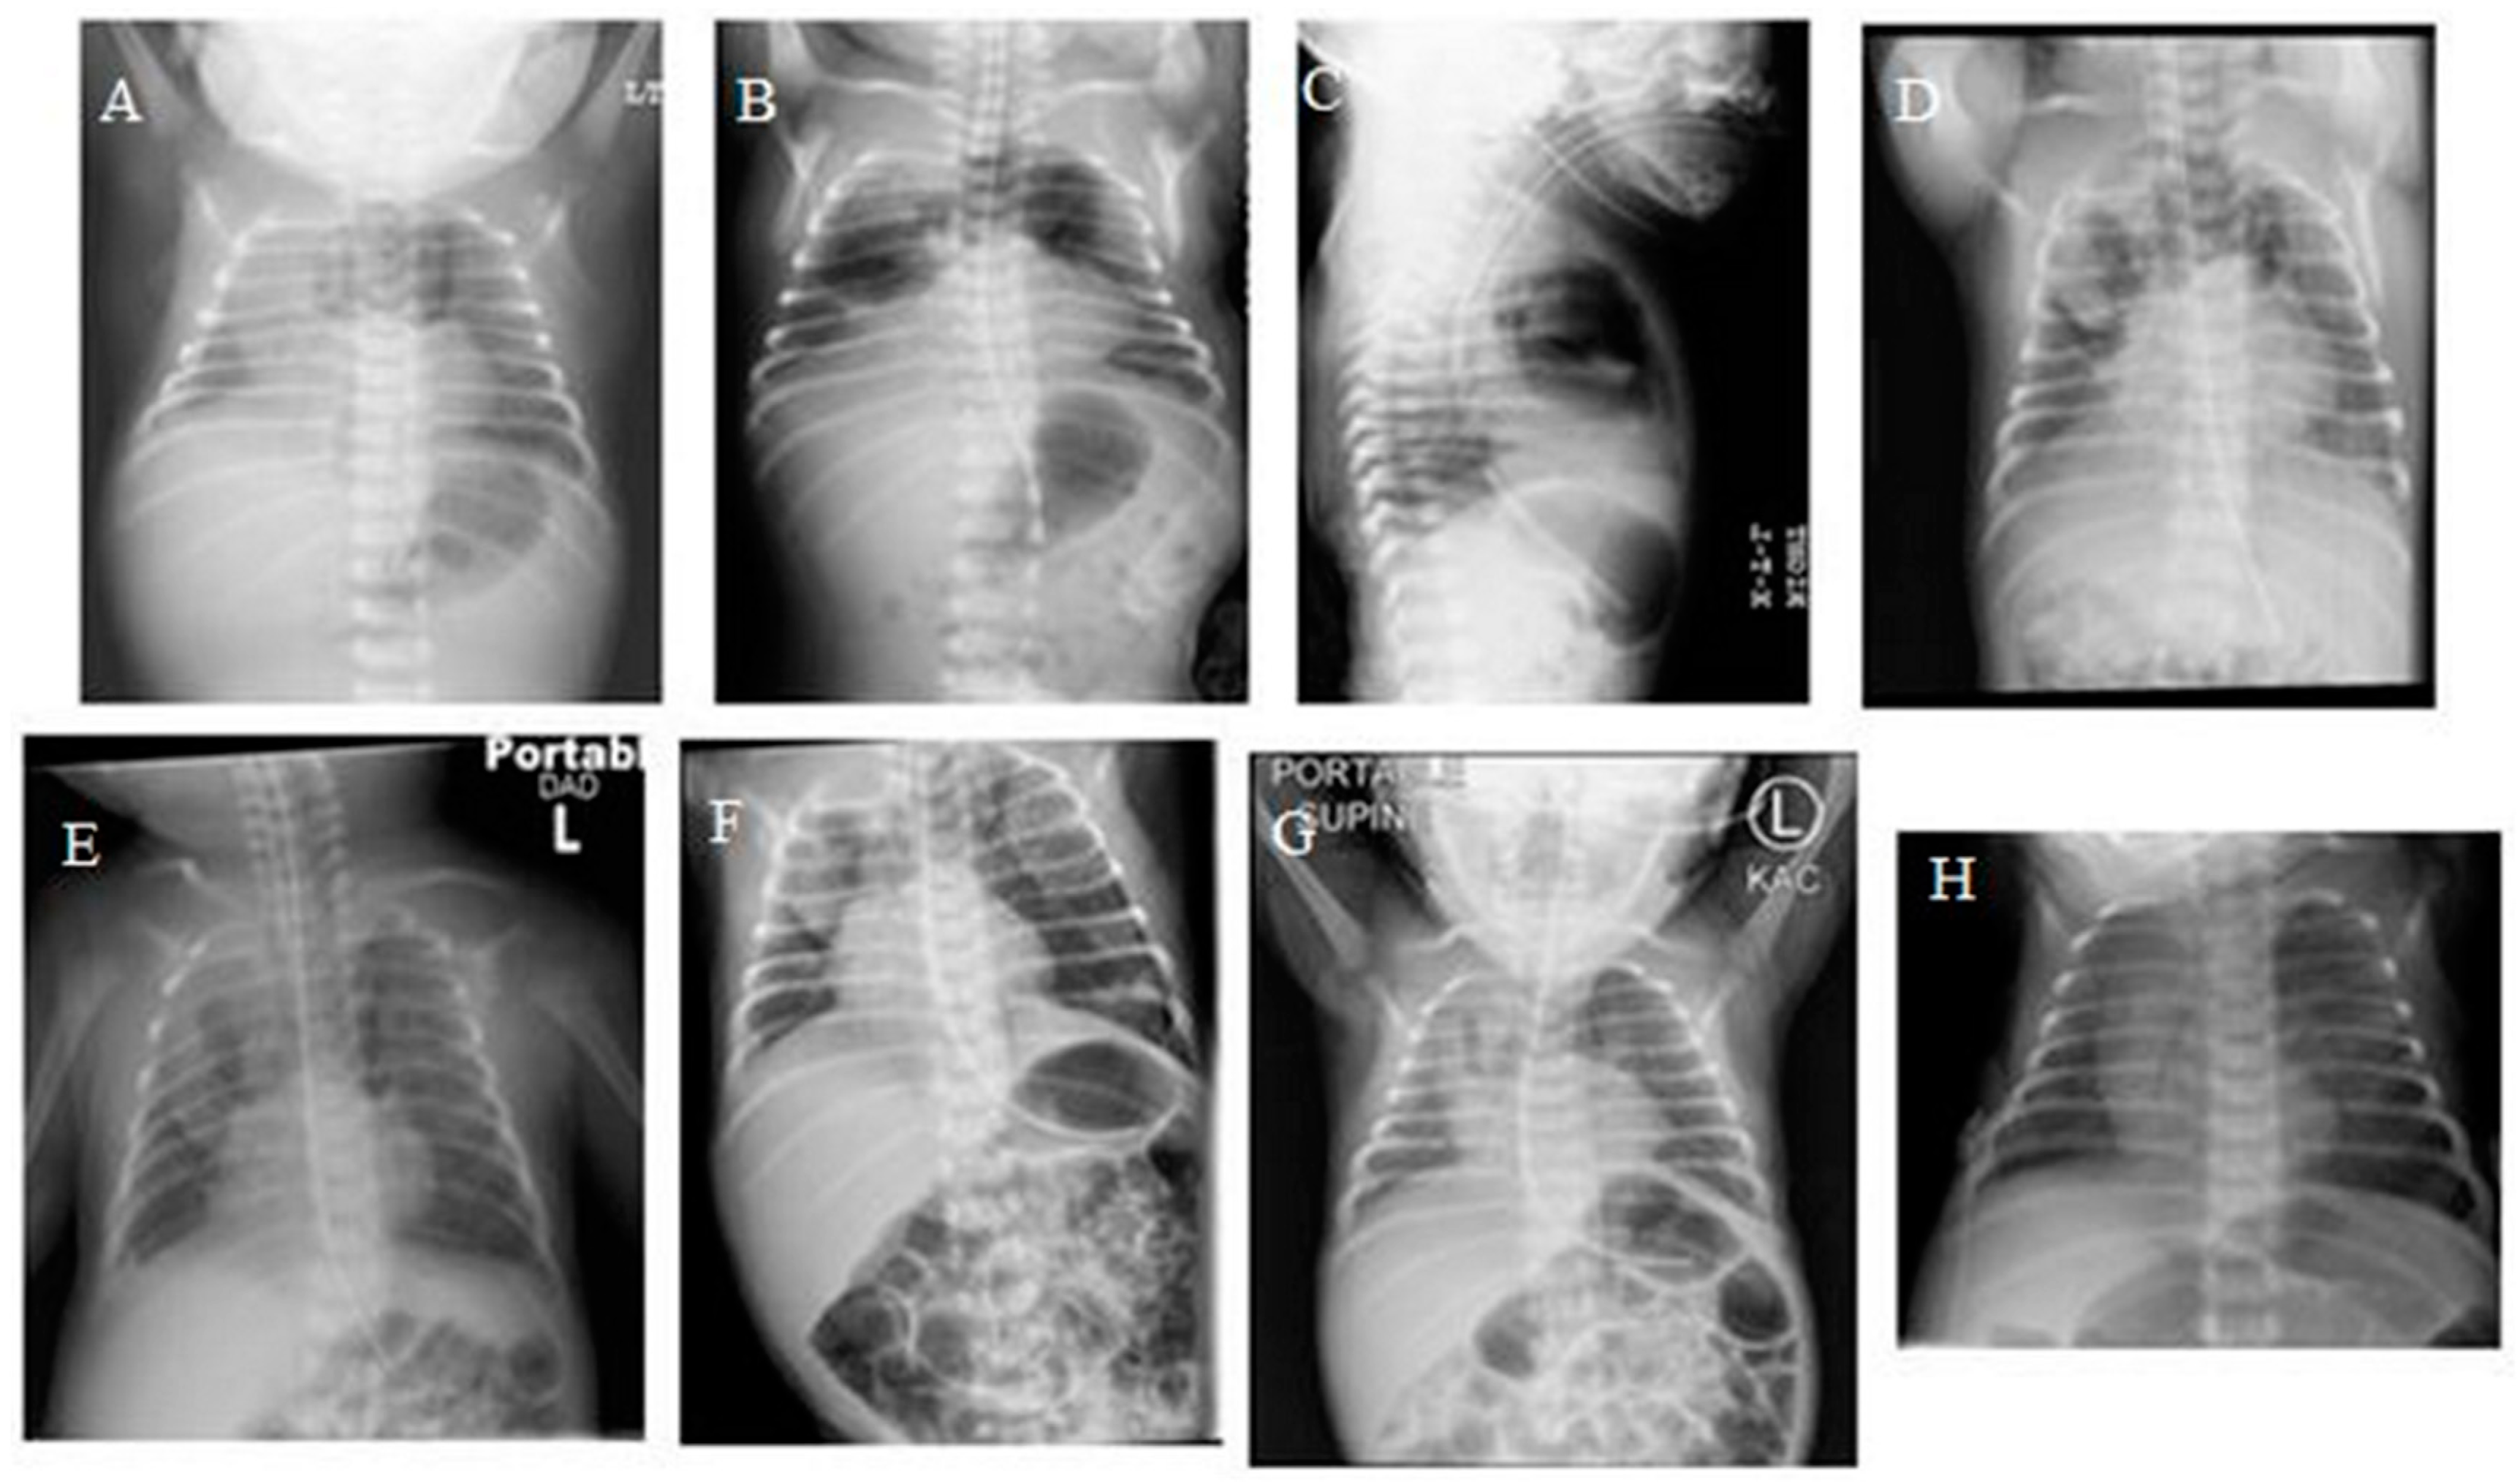

Pneumomediastinum Mimicking Congenital Pulmonary Airway Malformation

2. Case Summary